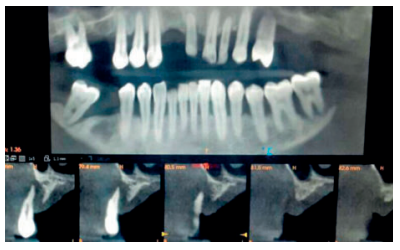

Introducción: La inclusión de caninos tiene una alta incidencia y plantea varias complicaciones clínicas, siendo de vital importancia el diagnóstico precoz y exacto para minimizar los riesgos y complicaciones derivadas. El objetivo de este trabajo es analizar, utilizando como referencia las líneas planteadas por Alqerban, la efectividad de las dos dimensiones en el diagnóstico volumétrico de la inclusión de los caninos maxilares.

Métodos: Seleccionamos 27 pacientes con 36 caninos maxilares incluidos que se realizaron estudio de ortodoncia con ortopantomografía y tomografía computarizada de haz cónico (Cone Beam Computed Tomography, CBCT) del maxilar en la Clínica Universitaria de la Universidad Europea. Se trazaron tres líneas de referencia basándose en la distancia de la cúspide del canino al plano oclusal (L1), a la línea media (L2) y a su lugar ideal de erupción (L3), tanto en la ortopantomografía como en el CBCT. Como valores de referencia ideales seleccionamos un grupo control de 36 caninos maxilares erupcionados.

Resultados: Se compararon los resultados en dos y tres dimensiones mediante la prueba T de Student, tras comprobar su distribución normal mediante la prueba de contraste de Anderson-Darling. No se obtuvo significación estadística (p>0.05) para ninguna de las variables estudiadas.

Conclusiones: El uso del CBCT es vital para asegurar un buen diagnóstico en cuanto a la posición del canino y su relación con estructuras adyacentes y así establecer un plan de tratamiento adecuado. Aun así, la ortopantomografía aporta información suficiente para la planificación inicial.

Radiographic diagnosis of impacted maxillary canines: Comparison between two and three dimensions

Introduction: An impacted canine is a very common condition and raises several clinical complications. Early and exact diagnosis is important in order to minimise the risks and subsequent complications. The objective of this study is to analyse the effectiveness of two dimensions in the volumetric diagnosis for impacted maxillary canines, using the lines proposed by Alqerban as a reference.

Methods: An orthodontic study of the maxilla using orthopantomography with cone beam computed tomography (CBCT) at the Madrid European University Clinic was performed on 27 patients selected with 36 maxillary impacted canines. Three reference lines were drawn based on the distance from the cusp of the canine to the occlusal plane (L1), to the midline (L2) and to its ideal eruption site (L3), in both the orthopanthomography and the CBCT. As ideal reference values, we selected a control group of 36 erupted maxillary canines.

Results: The results were compared in 2 and 3 dimensions using the Student’s t test, after verifying their normal distribution using the Anderson-Darling contrast test. Statistical significance (p > 0.05) was not obtained for any of the variables studied.

Conclusions: The use of CBCT is vital to ensure good diagnosis of the canine position and its relationship with adjacent structures and thus establish an adequate treatment plan. However, orthopantomography provides sufficient information for initial planning.